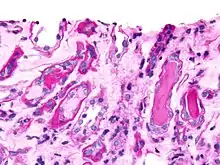

Waxy casts

Thought to represent the end product of cast evolution, waxy casts suggest the very low urine flow associated with severe, longstanding kidney disease such as kidney failure. Additionally, due to urine stasis and their formation in diseased, dilated ducts, these casts are significantly larger than hyaline casts.

- They are cylindrical.

- They possess a higher refractive index.

- They are more rigid, demonstrating sharp edges, fractures, and broken-off ends.

Waxy casts are broad casts, which is a more general term to describe the wider cast product of a dilated duct, and are seen in chronic kidney failure.